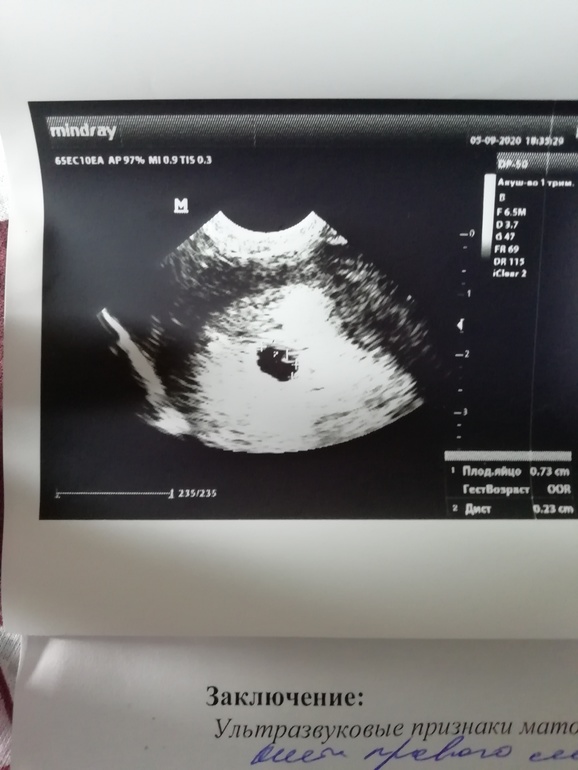

Видно только плодное яйцо

ФолликулометрияПривет всем! Скажите пожалуйста это нормальное что эмбриона ещё не видно? Вот что написали на узи... Овуляция была 12-14 августа... В об щем я что-то переживаю, сама не знаю чего и как 🤦♀️надеюсь все нормально будет

Я сегодня была на УЗИ, плодное яйцо 12 мм, а эмбрион около 1мм, его даже записывать не стали, поэтому рано еще Вам)

Вчера была на узи, овуляция тоже была примерно 14 августа, увидели так же только пя 7мм, так что все у нас хорошо))

Ну конечно это нормально, что эмбриона не видно! У вас только 5 акушерских недель, очень рано! чтоб наверняка увидели эмбрион и СБ идите в 7 полных, или хотя бы не раньше 6.5

У вас акушерский 5 недель,на таком сроке только плодное и видно,все соответствует сроку